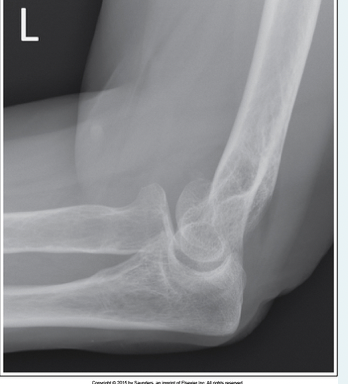

Which of the following positioning errors has occurred in this lateral elbow image?

a.Forearm is not on the same plane as the IR

b.Central ray is angled 30 degrees towards the shoulder

c.Elbow is rotated internally

d.Elbow is not flexed 90 degrees

A